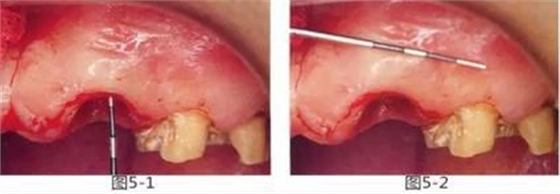

圖5-1,2

存在齦下齲壞。術(shù)前的穿刺檢查表明,從齦緣到牙槽嵴頂?shù)木嚯x在2mm以內(nèi)。角化齦寬度為5mm左右。

圖5-3~5

切開(kāi)牙齦至膜齦聯(lián)合處,形成半厚瓣。此時(shí)要注意手術(shù)刀的切入角度,謹(jǐn)慎操作以防造成齦瓣穿孔。